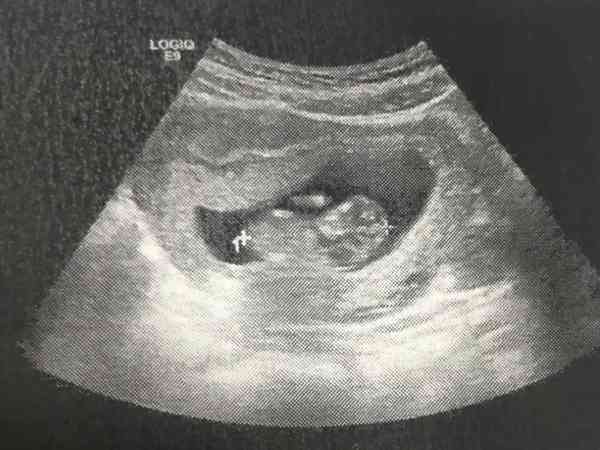

A級精子兩三個的北醫三院求子記錄,二代試管移植鮮胚一次成功

我和我老公2019年1月份領的證,我倆當時約定先不要寶寶,過兩年二人世界再要。但是同年七八月份我老公就覺得自己的精子有問題鬼使神差的去醫院檢查了,我當時還一直安慰他說沒事兒,因為之前覺得不孕不育這種事兒只有在公交車的廣告上看見過。2021年6月8號,產假倒計時還有最後一天,寶寶睡著了。閒來無事想記錄一下自己的試管之路。我的試管之路感覺離自己還是很遙遠,但是現實往往就是這麼會給人開玩笑。一查人家當時...